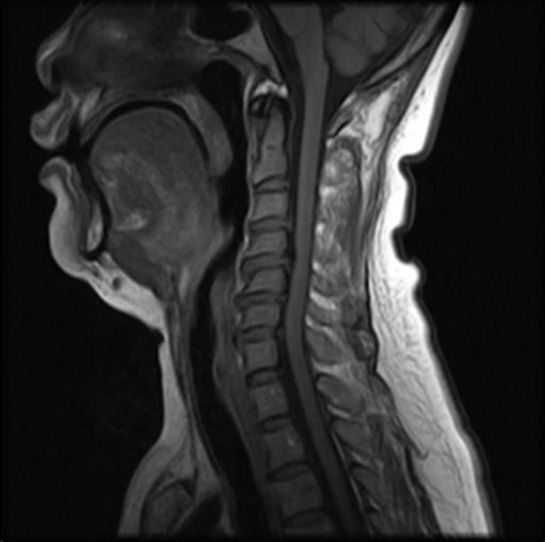

OSM70A superconducting MRI is the most advanced open MRI system. Thanks to its innovative magnet design and the optimization of a large number of imaging methods, the system combines with the advantages of traditional low field permanent MRI imaging systems and high field superconducting MRI.

(2)A series of innovative designs on imaging methods and image reconstruction algorithms overcome the difficulty of magnets. It fully achieve the characteristics of rapid imaging speed, high signal noise ratio and clear image display of superconducting MRI. The magnetic intensity of 0.7T system is higher than the traditional permanent MRI. And also its vertical field design is more conducive to the reception of MRI signals, making its signal noise ratio which is equivalent to the traditional superconducting 1.0T MRI system.

(3)OSM70A superconducting MRI system combines with the advanced sequence and application which used on 1.5T MRI . It also provide with comprehensive scanning software packages with the strong support of hardware and software platform. It is the best platform for imaging diagnosis and intervention treatment.